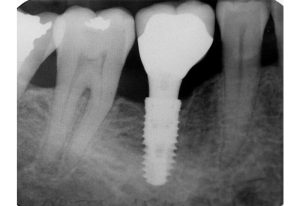

Рентгенологічне обстеження є важливою частиною імплантації зубів. Воно дозволяє лікарю оцінити правильність встановлення імпланта та контролювати процес його приживлення. Для пацієнта ж часто цікаво, як саме виглядає імплант на знімку.